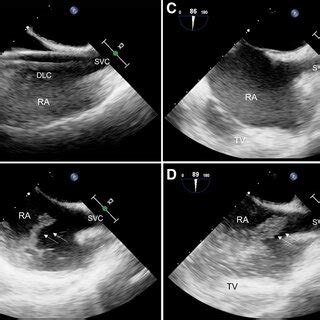

Hey guys! Ever wondered how those crystal-clear images of your heart’s big veins are captured during an echocardiogram? Well, it all boils down to the bicaval view echo probe position . This is super important for cardiologists and sonographers to accurately diagnose and understand what’s happening inside the heart. Getting this position right allows us to visualize the superior and inferior vena cava (the big veins bringing blood back to the heart) and the right atrium, giving a comprehensive view of the heart’s function. Let’s dive deep into how to nail this position and get those perfect images! This is critical for assessing right heart function, detecting issues like thrombus (blood clots), and measuring the size and function of the vena cava. Accurate probe placement is key to getting these measurements right and making sure patients get the best care.

So, why is this bicaval view so crucial? Think of the heart as a bustling city, and the vena cava are the highways bringing in all the traffic (blood) from the rest of the body. The bicaval view gives us a panoramic view of these highways as they enter the heart’s main station (the right atrium). This view is your go-to for checking the size and shape of these major vessels and how they function. This is especially vital when checking for clots, which can be deadly. It also helps in assessing the pressure within the right atrium, a key indicator of heart health. Furthermore, it gives a good look at the tricuspid valve, ensuring it’s working properly. This view is also super helpful in assessing patients with shortness of breath, chest pain or other symptoms related to heart problems, the bicaval view can provide crucial insights.

Alright, let’s break down the process step-by-step for the bicaval view echo probe position . First, you’ll need the right equipment: an ultrasound machine, the right kind of probe (usually a phased array), and some acoustic gel (that stuff that makes everything glide smoothly). The patient should be positioned in the left lateral decubitus position. This positioning moves the heart closer to the chest wall, making it easier to get clear images. Now, apply the acoustic gel liberally to the probe head. This helps eliminate air pockets and ensures good contact with the skin. Place the probe just below the sternum, aiming towards the patient’s right shoulder. Gently angle the probe and try to visualize the right atrium and the vena cava. Remember to keep the probe flat against the chest wall to get the best contact and minimize any loss of image quality. Slight adjustments are often necessary to find the sweet spot, the one where the images are super clear. Scan through the various angles to see which one gives you the best picture of the superior and inferior vena cava entering the right atrium.